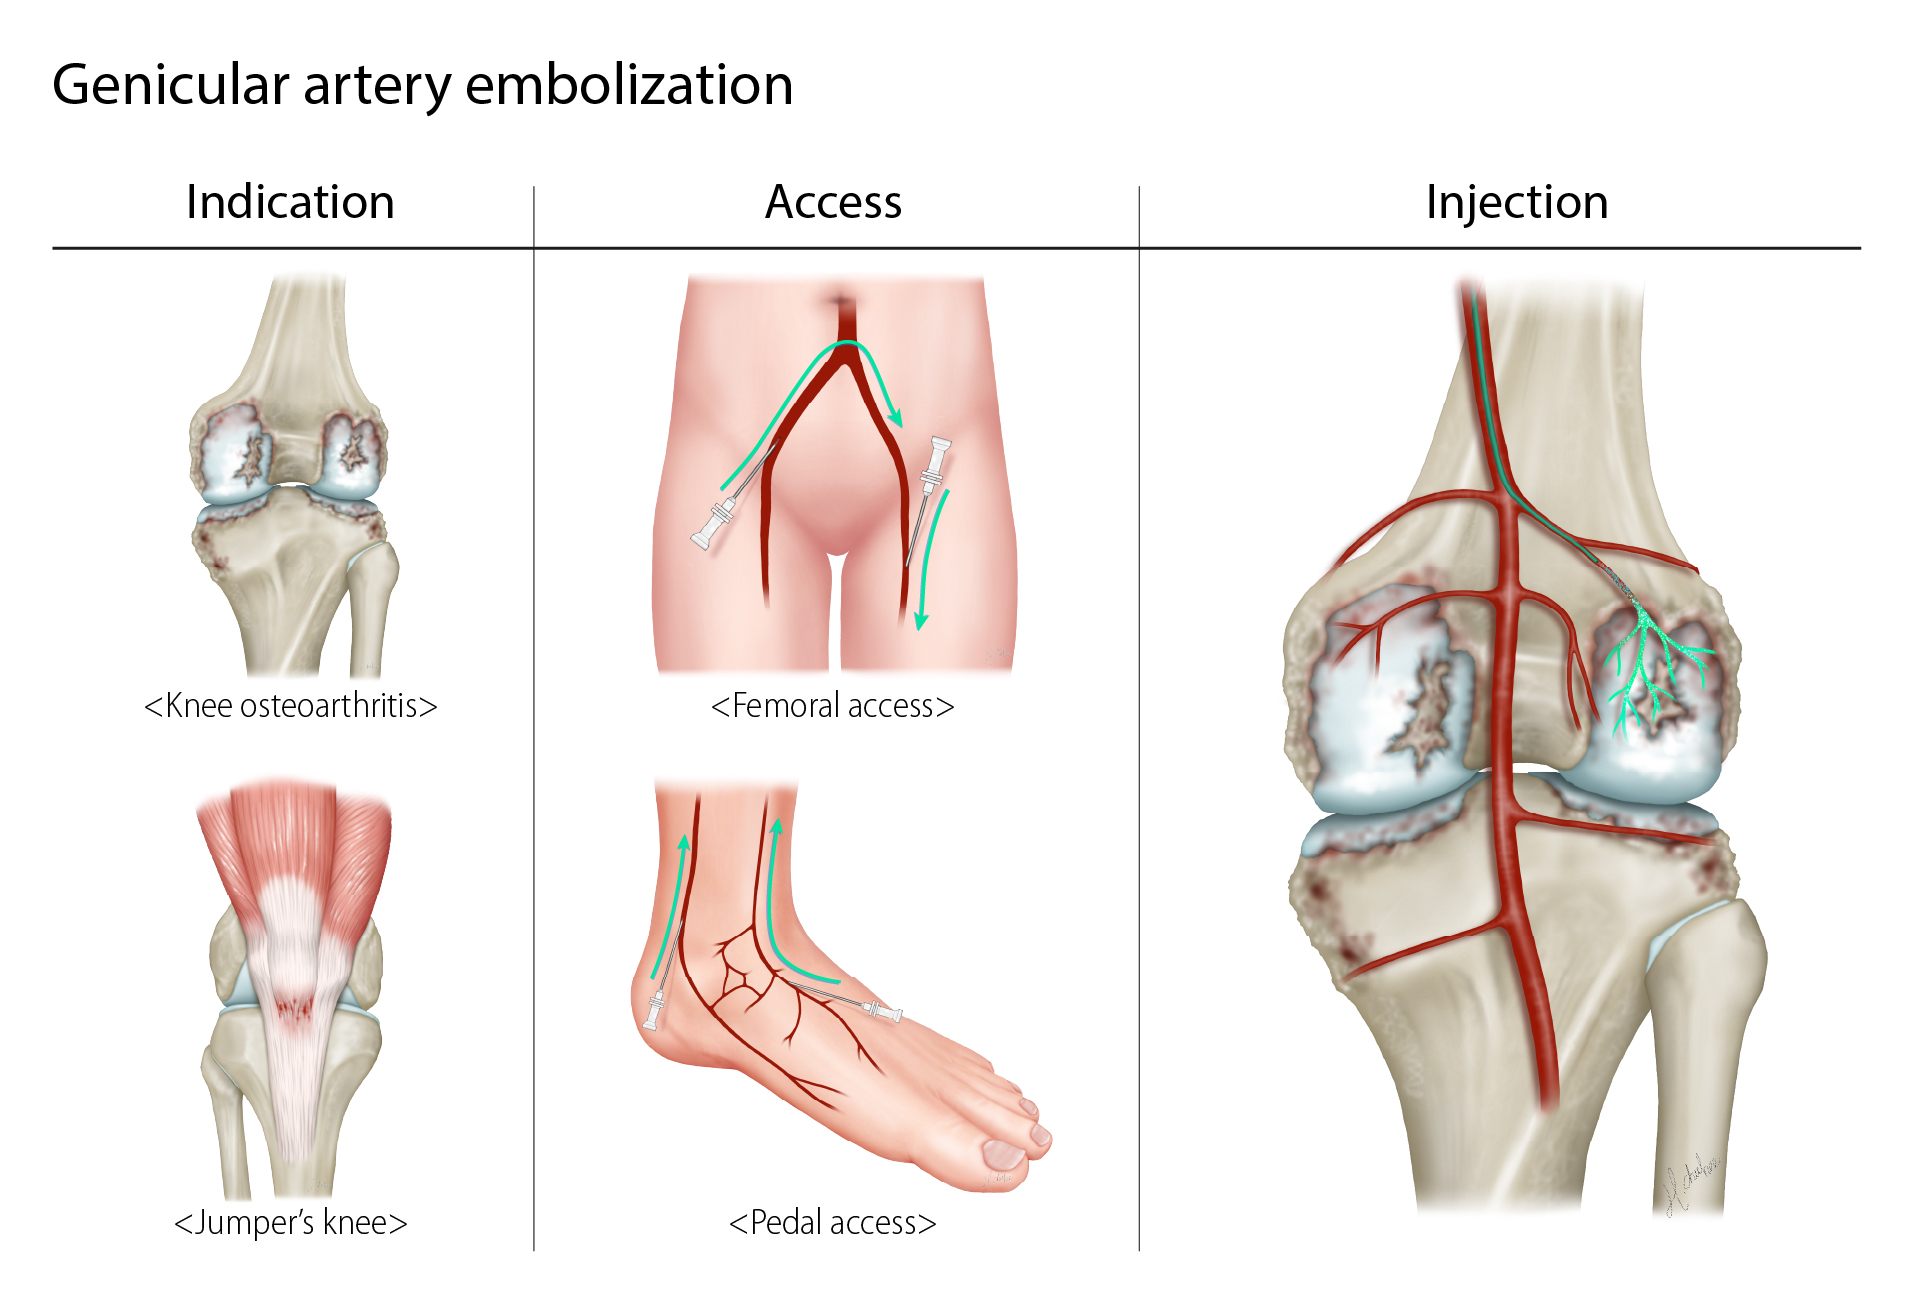

Genicular Artery Embolization (GAE) is a minimally invasive, image-guided procedure for treating chronic knee pain caused by osteoarthritis or related to chronic inflammation. It works by reducing blood flow to the inflamed areas of the knee, which can help relieve pain and improve mobility. Interventional radiologists will insert a small catheter (a thin hollow tube) into the artery of the patient’s upper thigh and, with the use of X-rays, guide the catheter to the arteries supplying the lining of the knee. Tiny particles are then injected through the catheter into these arteries, reducing the blood supply. This in turn reduces the inflammation associated with osteoarthritis, which alleviates the pain

- Knee osteoarthritis

- Jumper’s knee (patellar tendinitis)

How the Procedure Is Performed

- Performed by an interventional radiologist

- Done under local anaesthesia with light sedation for comfort

- A small catheter is inserted into an artery (usually in the upper thigh)

- Using X-ray guidance, the catheter is advanced to the small arteries supplying the inflamed areas of the knee

- Tiny microparticles are injected to block the abnormal vessels while maintaining normal blood flow

- The procedure usually takes about 1–2 hours and is performed as a day-stay treatment